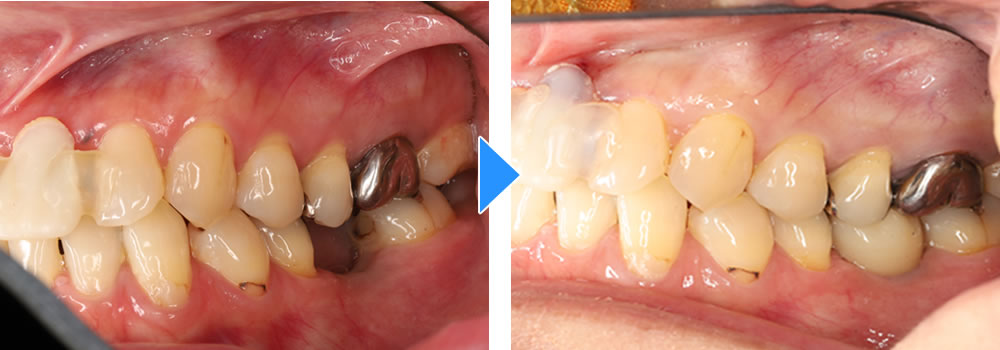

治療前後の比較

治療前後の比較画像です。患者さまにも色合い等大変、満足いただけました。